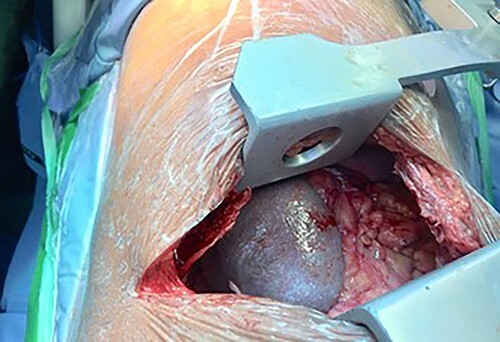

Following the CT scan and confirmation of diagnosis, a nasogastric tube was inserted. This drained 1.5 L of fluid over 2 h with a large quantity of air. A considerable improvement in the patient’s respiratory distress was noted with the respiratory rate normalizing and a follow-up CXR showed a dramatic reduction in the size of the intrathoracic stomach with a matching lung re-expansion (Fig. 3). She was brought to the operating room the following morning after appropriate resuscitation and electrolyte correction. The chest was entered via a seventh intercostal space leftposterolateral thoracotomy revealing a 5-cm defect in the left dome of the diaphragm with an incomplete hernia sac with the stomach, greater omentum and spleen incarcerated inside the chest cavity (Fig. 4). Adhesions were released and the stomach, omentum and spleen were reduced into the abdominal cavity. The defect was primarily closed in two layers (double breasting). The patient was sent home on the fifth post-op day following an uneventful recovery. She was seen 6 weeks later and was doing well.

Figure 4.

Left posterolateral thoracotomy revealing herniated spleen, stomach and greater omentum.